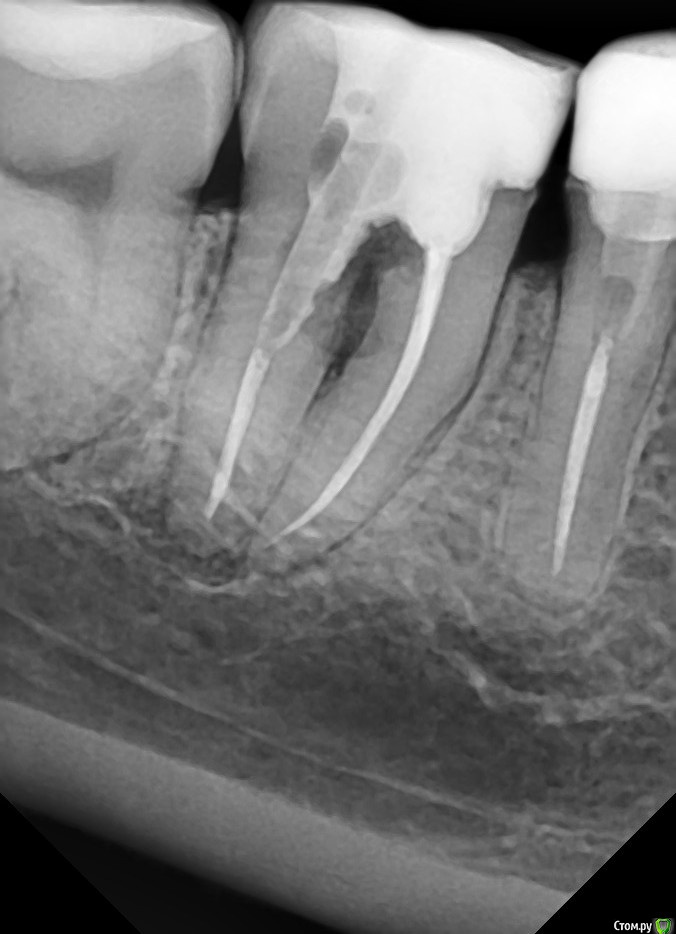

Возможно ли сохранить зуб 4.7? Прикрепляю 2 снимка: 1 - через месяц после эндодонтического лечения, 2 - через 5 месяцев после эндодонтического лечения.